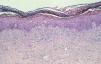

Una biopsia tomada de dicha lesión, puso de manifiesto extensas áreas de necrosis de queratinocitos y la presencia de un infiltrado inflamatorio liquenoide compuesto por linfocitos y algunos eosinófilos de localización perivascular e intersticial (fig. 2). Además, se apreciaba una metaplasia escamosa ecrina con obliteración de los ductos y zonas de necrosis de células ecrinas (fig. 3).

Fig. 2.--Infiltrado liquenoide compuesto por linfocitos y algunos eosinófilos de localización perivascular e intersticial, con extensas áreas de necrosis de queratinocitos. (Hematoxilina-eosina, x25.)